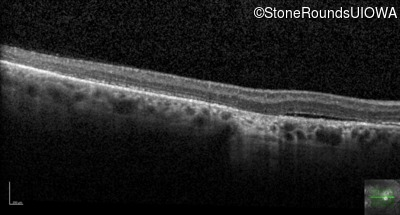

Optical Coherence Tomography - Right - 20/100

Exemplar / OCT Stack